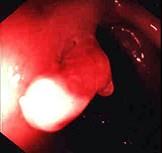

问题 男性,40岁,15年前出现解黏液血便,当时诊断为溃疡性结肠炎,一直服药治疗,病情反复,今大便正常已2年。查体浅表淋巴结无肿大,腹软,无压痛,未及包块,肠鸣音正常。肠镜检查图片如下,最可能是 ( )

选项 A、肠结核 B、结肠腺瘤 C、结肠癌 D、Crohn病 E、溃疡性结肠炎中的炎性息肉

答案 E